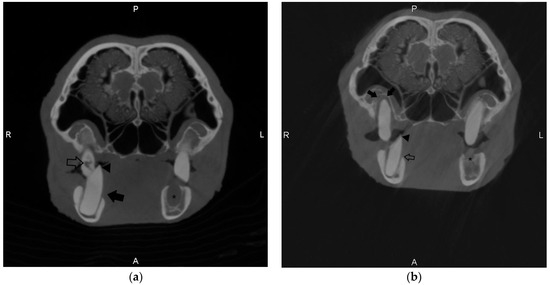

Figure 2. Transverse images of the skull of Case 1 using cone-beam computed tomography (CBCT) taken at two time points. Images were captured at the level of the third molar tooth. (a) Taken in 2019 and shows horizontal bone loss affecting the right third mandibular molar (black arrow), a large point of the right third mandibular molar (arrowhead), caries-like lesions associated with the crown of the right third maxillary molar tooth (open arrow), and a missing left third mandibular molar tooth with an associated alveolar defect (Asterix). (b) Taken in 2021 and shows significant alveolar bone loss surrounding the tooth root of the right third maxillary molar (solid arrows) and continued horizontal bone loss associated with the right third mandibular molar tooth (open arrow). The right third mandibular molar is axially displaced relative to the maxillary molar, and there is a significant point associated with the right third mandibular molar. The left third mandibular molar tooth is absent, and there is an alveolar defect at the level of the missing tooth (Asterix).

Cone-beam computed tomography was first performed in October 2019 (Figure 2, Image A). At this time, this patient already had a significant dental history requiring extractions in April of 2012, December of 2014, July of 2015, and August of 2017 (See Table 1, Case 1). CBCT showed three areas of apical lysis identified in the left and right maxillary third molars. A diagnosis was made of alveolar bone loss, secondary to periapical disease and severe malocclusion. No clinical signs were appreciated at that time. Upon intraoral examination, purulent material was associated with the affected teeth. Follow-up CBCT was performed in September of 2020, and moderate progression of the apical lysis was appreciated on the same tooth (left and right maxillary third molar), with the identification of a root remnant present on the right mandibular first molar (extracted in 2012). This root remnant was not observed in the CBCT scan performed in 2019, or in standard skull radiographs performed concurrently at the time of examination. A diastema was noted upon intraoral examination in this region, but no other radiographic or intraoral pathology was identified, and CBCT was considered helpful in the identification of the root remnant. Follow-up CBCT was again performed in November of 2021 (Figure 2, Image B), showing additional root remnants present in the left mandibular first and second premolars and second molar (extracted in 2017) and a missing third molar. These lesions were associated with alveolar bone loss, as well as progressive severe malocclusion. A diagnosis of progressive alveolar bone loss was provided. The remaining tooth on the left mandibular arcade (the first molar) had an elongated crown and was rostrally displaced with a lingual point. Horizontal bone loss was appreciated in the right mandibular third molar. Caries-like lesions (focal loss of attenuation in the crown) were observed on the scan observed in 2021 and were not observed on earlier CBCT scans. CBCT was considered clinically helpful in documenting the progression of tomography lesions in this patient.